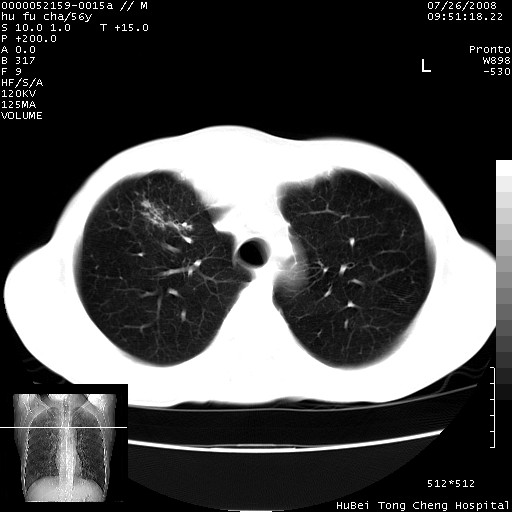

以下是引用zsl6918在2008-8-25 22:47:00的发言:[br]胸骨,胸椎及肋骨均可见多发转移表现,肝内低密度结节不除外转移。原发灶可能在右肺。双侧可见支扩表现。